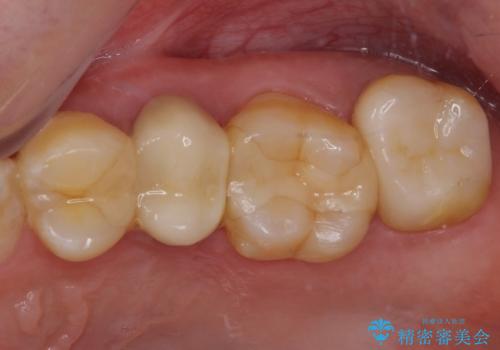

冷たいものがしみて奥歯が痛い 気になる歯並びも治した